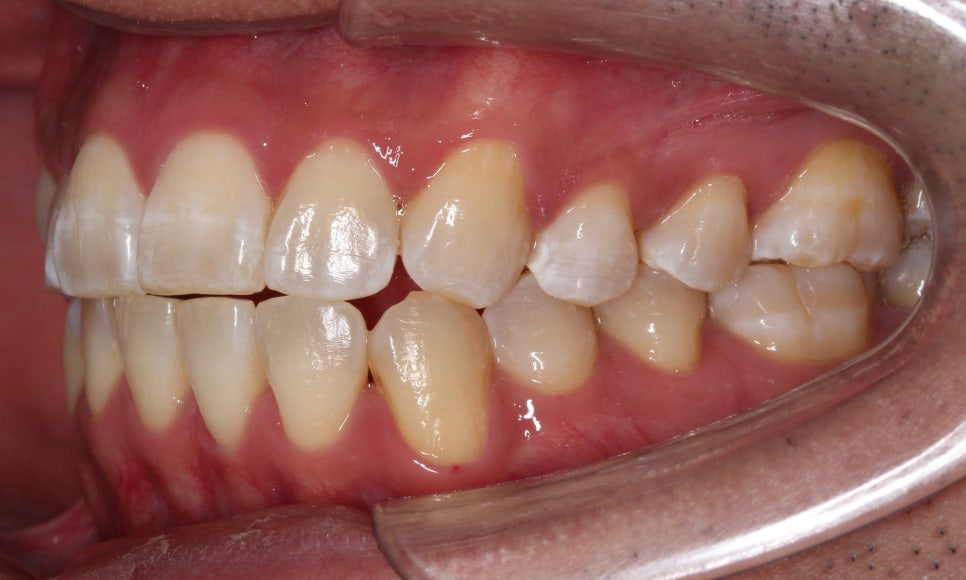

치료 후 6개월 정도 지났습니다.

그 사이에 #12 치아를 꺼내기 위해

구치부에 bite resin을 올려뒀었습니다.

촬영할 땐 bite resin을 제거 후 촬영했습니다.

거꾸로 물리는 치아는

bite를 올리지 않으면

교합이 간섭되어 나오기가 어렵습니다.

제 눈에는 앞니들 교합이 조금 더

긴밀해지면 좋을 것 같고

#12 치아도 치축을 개선하면 좋을 것 같아서

wire에 bending을 줘서 조절을 했습니다.

환자분이 직접 꼈다 뺐다 하는 고무줄을

이용하여 전치부 교합을 조금 더

긴밀하게 마무리했습니다.

배열이 처음보다 훨씬 좋아졌습니다.